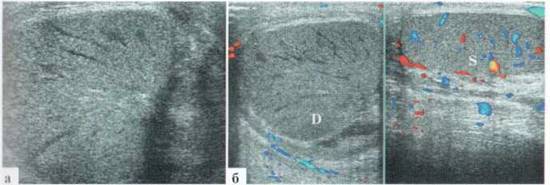

УЗИ ОРГАНОВ МОШОН К И: определяется резко выраженное утолщение мягких тканей мошонки (отек) без эхопризнаков нарушения структуры яичек и признаков жидкостного компонента в оболочках (рис. 2.4.2). Интратестикулярный сосудистый рисунок сохранен.

ЗАКЛЮЧЕНИЕ: эхопризнаки отека мягких тканей мошонки.

Рис. 2.4.2. Клинический пример № 12. Разные сканы мошонки; D — правое яичко; S — левое яичко